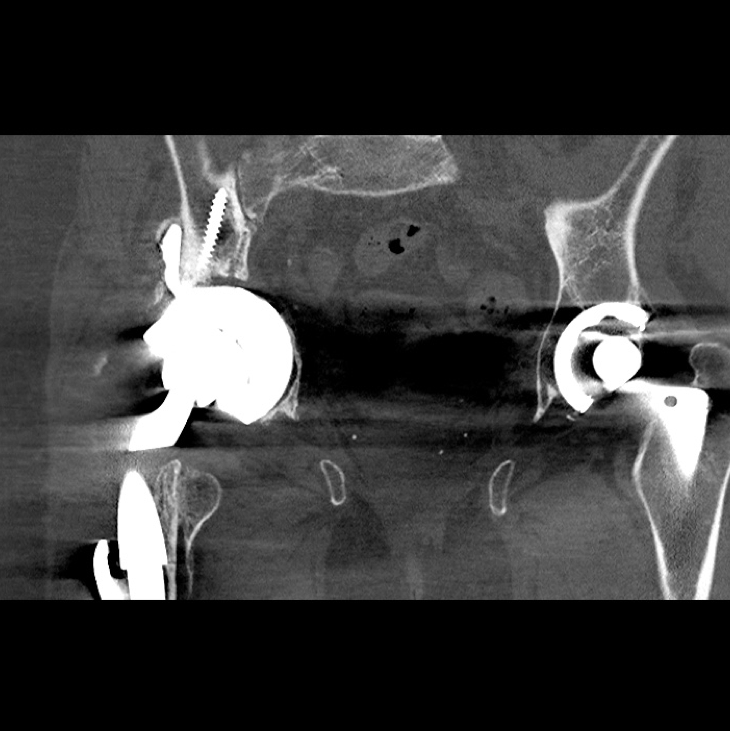

Post-Op CT scan 7-months - This is a post-operative CT scan taken at 7-months post-op. There is no migration of the implant compared to the pre-operative radiograph